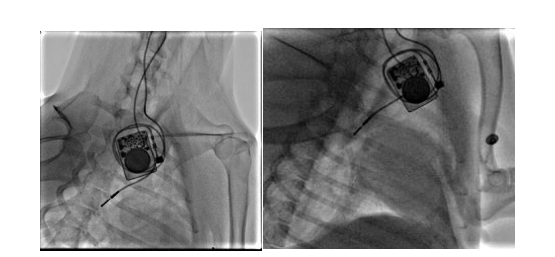

团队构建犬的慢性房颤动物模型,分析无创体表心电标测和有创心外膜心电标测系统采集的心电信号的相关性。我们顺利获得经颈静脉介入(图10)和右外侧开胸小切口(图11)两种方法建立快速起搏右心房的犬慢性房颤模型

图9 经颈静脉介入路径构建右心房快速起博犬的慢性房颤模型

图10 经右侧胸部小切口构建右心房快速起搏犬的慢性房颤模型